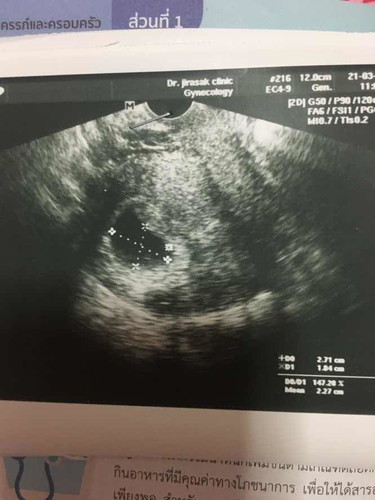

ของเราก็ประจำเดือนมาวันสุดท้าย วันที่ 14มกราเหมือนกันค่ะ นี่ภาพอัลตร้าซาวน์ ตอน 6 วีค 3 วัน เห็นตัวน้อง ได้ยินเสียงหัวใจเต้นแล้วค่ะ